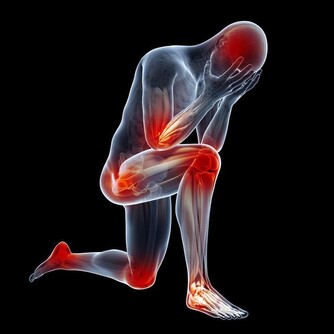

肌肉症狀另一方面,不論是靜脈還動脈中存有血栓,手臂肌肉都會明顯受到影響。

常見的包括肌肉痙攣、手臂酸痛無力、上肢麻木等。